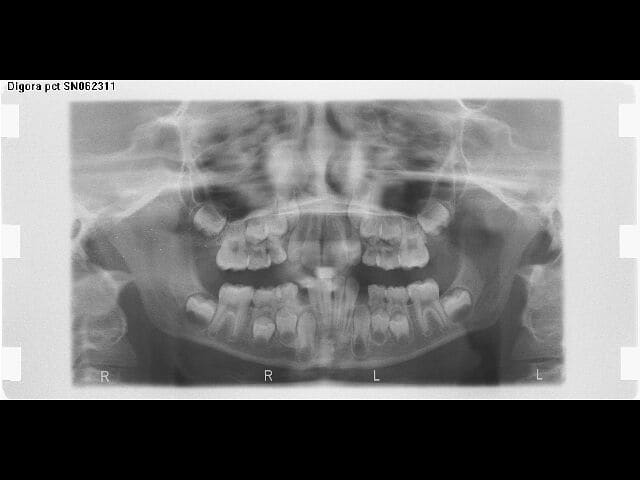

jazz,est ce que tu peux envoyer la pano?

Ci joint le pano du cas de gémination de 21 du petit Cham.

Je serais content si Dancha, Ploc et autres pouvaient me donner également leur avis

pffff...quelque chose m'echappe...vous arrivez vraiment a visualiser la taille et la forme de la racine? ou?